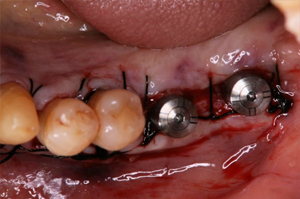

再生した骨にインプラントを埋入

上部構造を装着しました

インプラント2次手術(頭出し)